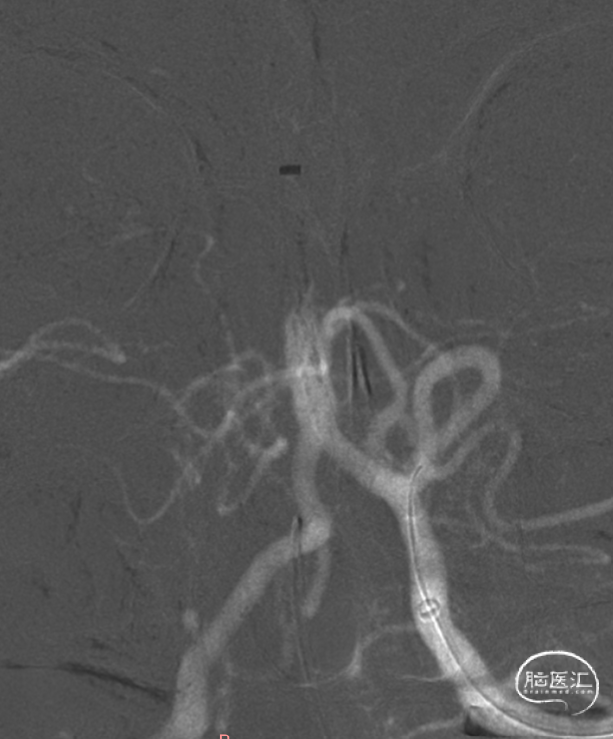

左侧椎动脉造影。

6F 125cm 通桥银蛇®颅内支持导管到位。

6F 125cm 通桥银蛇®颅内支持导管抽吸过程。

负压抽吸2次,基底动脉顶端部分再通,见栓子向双侧大脑后动脉逃逸。